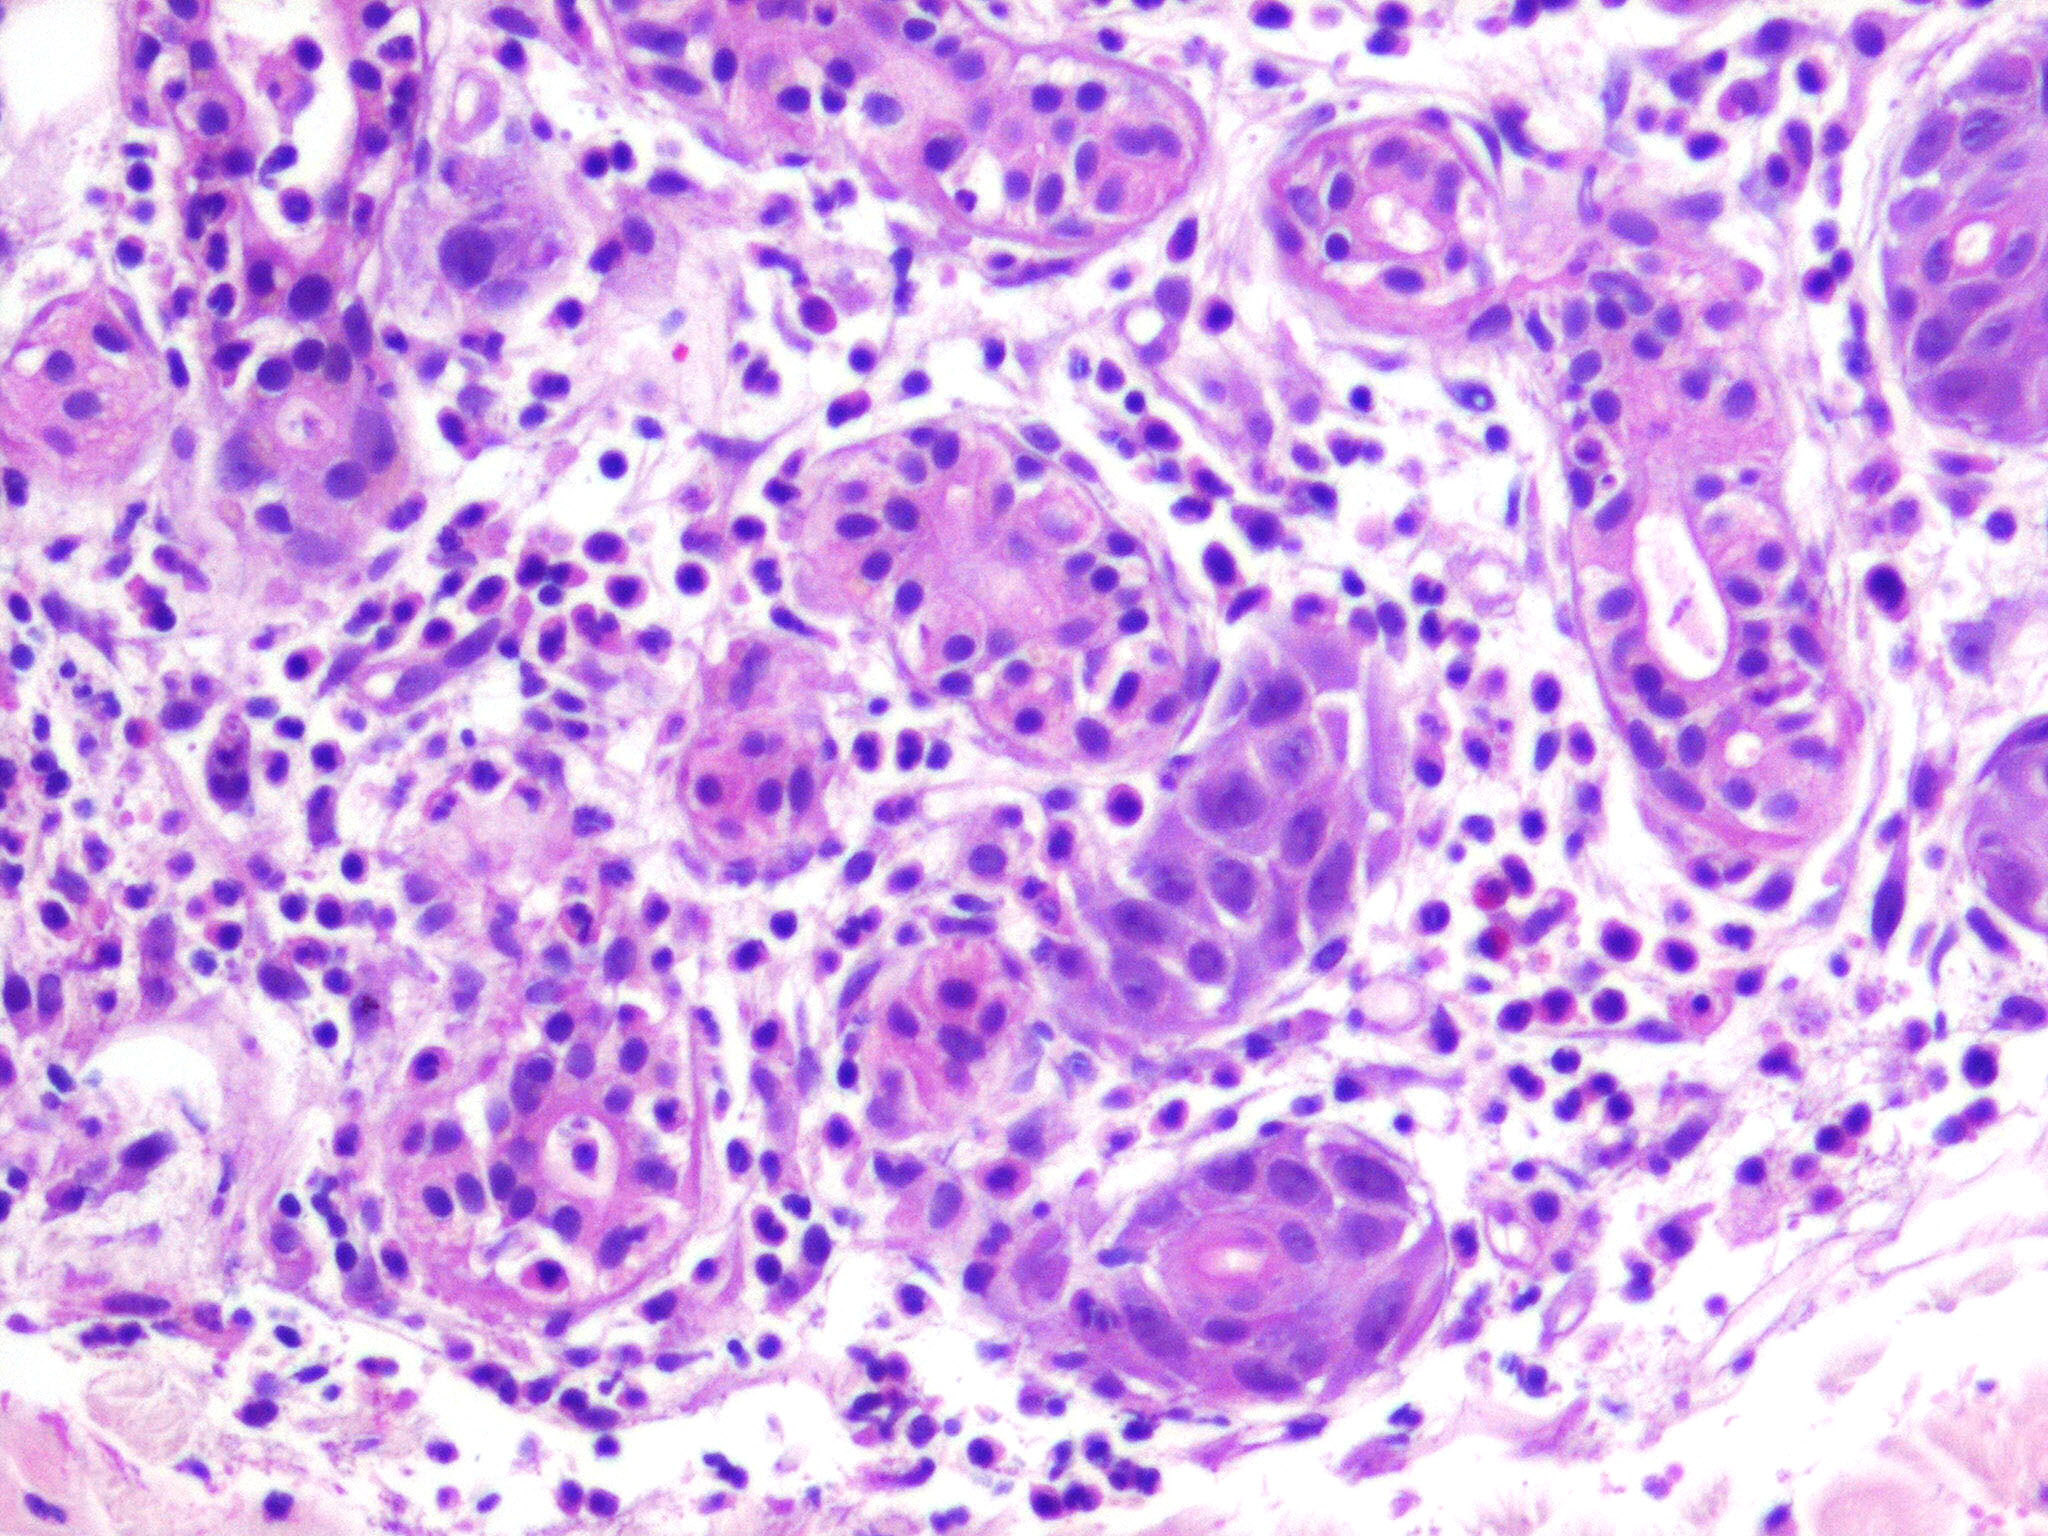

Neutrophilic eccrine hidradenitis = التهاب الغدد العرقية الناتحة بالمعتدلات

OLYMPUS DIGITAL CAMERA